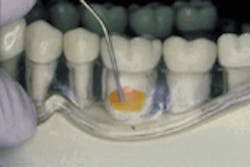

The application of Atridox is shown at the beginning of treatment (left) and four months later (right).